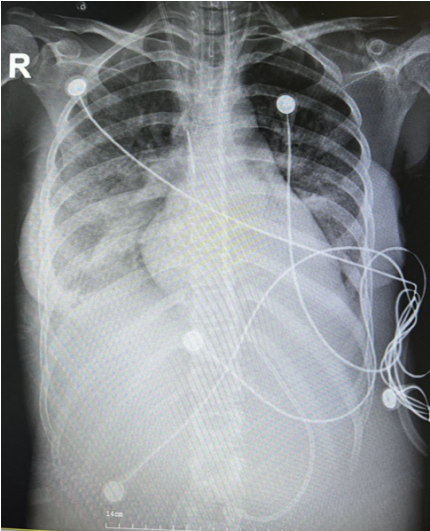

6月23日床旁胸片见右下肺少许炎症(图1)

图1  患者胸部X线片(2022年6月23日)